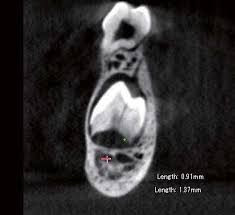

乳歯の歯根が吸収していきます

乳歯の歯の根が段々と吸収されて短くなることで揺れが増してきます。いわゆる「歯がグラグラしてきた」状態になるのです。